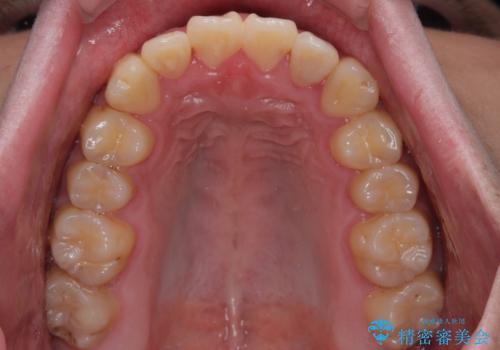

気になっていたクロスバイトは速やかに改善され、1年間で治療を終えることができました。

治療開始前は汚れが多く、全体的に歯肉が腫れていましたが、矯正治療を通して腫れも少しずつ改善されました。